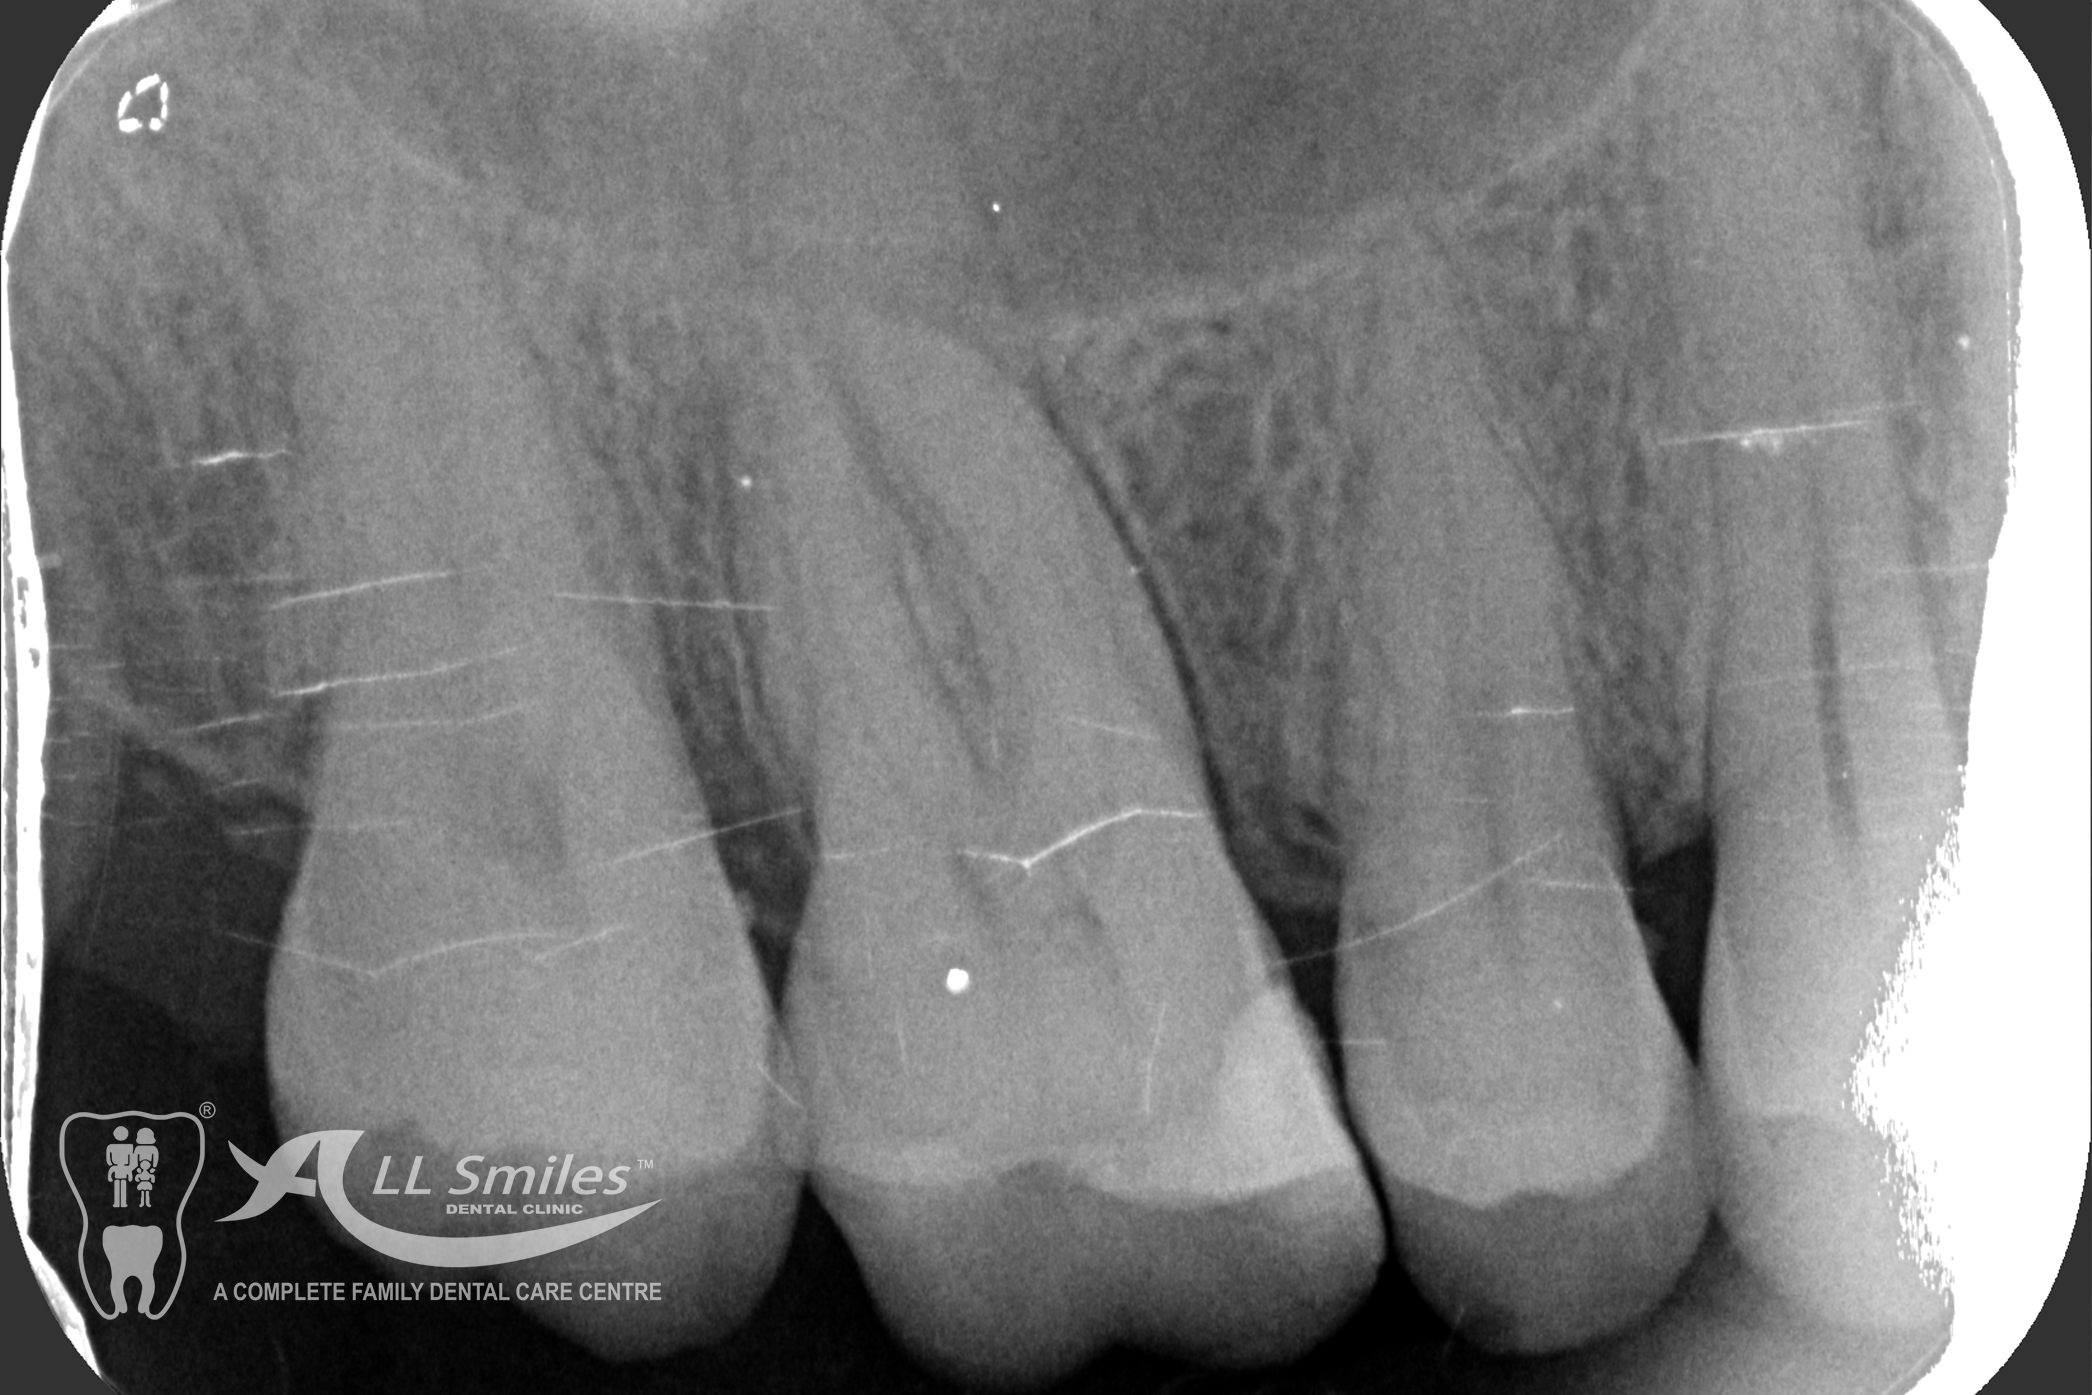

Successful tooth implant procedures require a foundation of healthy bone and gums. Before starting an implant procedure, we’ll assess your health and work with you to create a plan to resolve gum disease or other issues. Expect your first visit to take about 90 minutes and include an exam, x-rays, thorough cleaning, and plenty of time to speak with your dentist.

The dental implant procedure is divided into stages. The first stage involves the placement of the implant into the jawbone, which usually takes 1-2 hours. After this, there is a healing period of 6-8 weeks during which the implant fuses with the surrounding bone tissue. Once the implant has healed, a small connector called an abutment is attached to the implant, followed by the attachment of a dental crown, bridge, or denture.